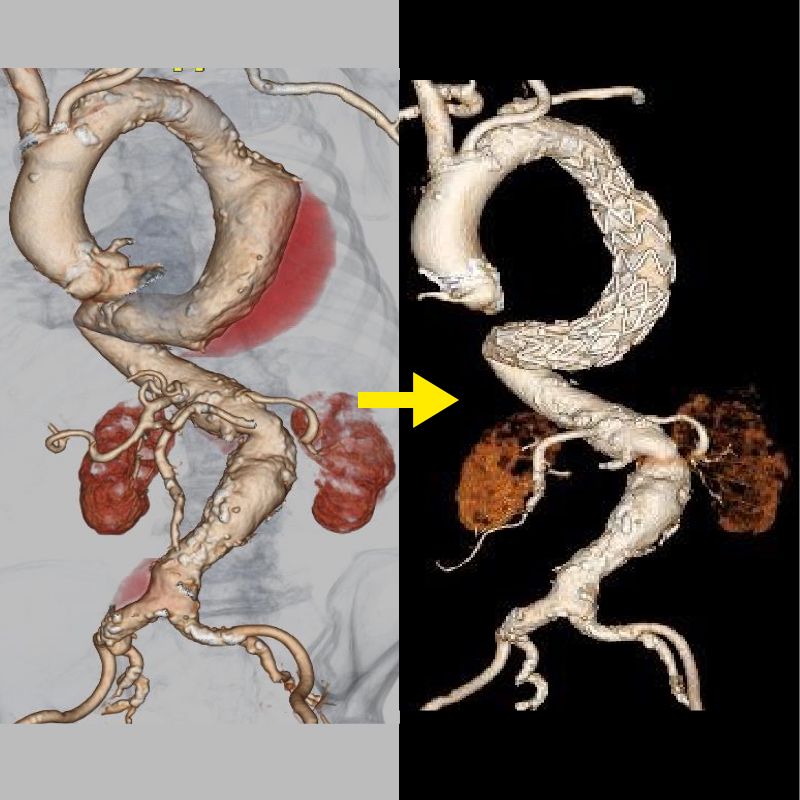

胸部大動脈瘤に対して施行したステントグラフト内挿術

大動脈解離は、突然発症する疾患で、大動脈に亀裂が入り、血管が裂ける病気です。急性期には解離した血管壁が薄くなり、破裂を起こす可能性や主要臓器への血流が遮断されることで臓器障害を引き起こす可能性があります。治療法は、動脈瘤と同様に人工血管置換術とステントグラフト内挿術があり、病態に合わせて適切な治療を行います。

当院では大動脈解離の治療法にオープンステントグラフトを導入しています。オープンステントグラフトは広範囲の解離部分に対して治療効果が得られる利点があります。

解離した場合によっては、ステントグラフト治療が適応になることがあります。大動脈解離に対するステントグラフト治療は専門性が高く、心臓血管に特化した当院の大動脈専門スタッフが慎重に判断して施行しています。

白矢印が大動脈の亀裂、赤矢印はステントグラフトで亀裂を閉鎖していることを示す。